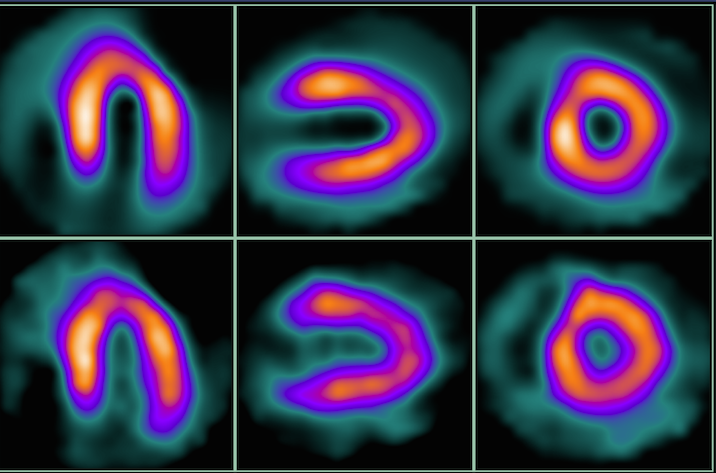

UltraSPECT Inc. announced the 10th anniversary of the U.S. Food and Drug Administration (FDA) approval of its Wide Beam Reconstruction (WBR) technology.